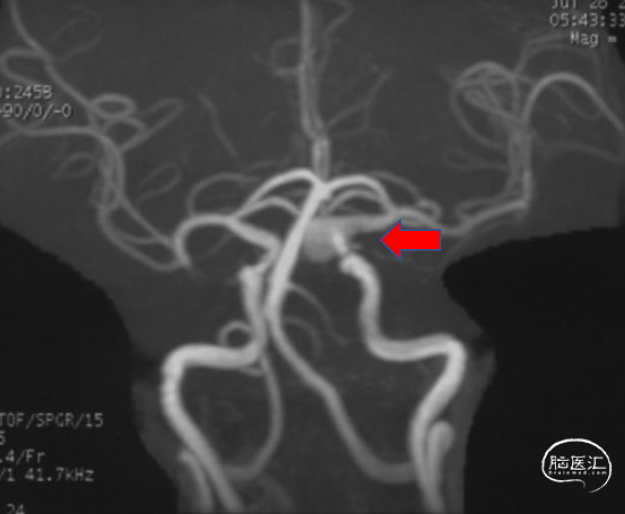

术前影像学资料

2022-7-26 MRA

诊断:左侧颈内动脉眼段大型动脉瘤。